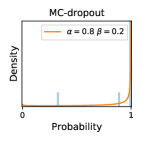

To model how different classifiers will respond to a given input , we assume that the prediction from classifier is sampled from a beta distribution that is characterized by two parameters by and . We further assume that is fixed to the same constant value for all ’s. Under this assumption, each input can be described by ( can be calculated since is fixed), easing further analysis. The Severity Level (SL) of the case represented by image can be characterized by the parameter . The larger the value of , the more severe the case of is. When and are close, the case is ambiguous as the distribution shifts towards being symmetric (i.e. signifying much disagreement among classifiers) rather than being one-sided (i.e. consensus among classifiers that is negative or positive). We provide a set of examples in Figure 2 and also Figure S.8 in the supplementary materials showing how the beta distribution can be used to capture diverse predictions given by an ensemble learner.

5.1 Distribution of Uncertainty Scores

Distribution of Uncertainty Scores Across Different Severity Levels As explained in Section 3, each uncertainty metric essentially defines an order/ranking among the data points. We conducted an analysis to better understand what data will be assigned high uncertainty under a particular uncertainty metric . Picking out the highest ranked data points (), we calculated the ratio of data points from each SL. Figure 4 summarizes the results as box plots for the Kaggle-DR and the Messidor-2 datasets; additional detailed statistics can be found in Table S.1 in the supplementary materials. From the plot and table, SL1 & SL2 examples account for a higher proportion among the top-ranked uncertain examples across the three ensemble methods. This finding matches our intuition that incipient disease examples (SL1 & SL2) are more likely to be considered uncertain by ensemble methods due to their ambiguity.

In contrast, the MC-dropout method showed the worst overall performance among the three, as it can be seen from the high ratios of SL0 examples among the uncertain negatives in Figure 4. The histograms in Figure 2 provides another perspective to look into the phenomenon, where a decent proportion of MC-dropout model’s predictions on SL0 inputs entailed low confidence (far from 0 or 1), which from another angle explained why MC-dropout was less specific in terms of lower FNP; many no-DR inputs (i.e. SL0) were erroneously assigned high uncertainty by MC-dropout models.

It is still an open question why the evaluated MC-dropout networks signaled relatively high uncertainty on SL0 & SL3 & SL4 data that are less likely to be ambiguous. We conjecture that much of the “uncertainty” indicated by disagreement among test-time dropout samples actually reflects the stochastic nature of dropout networks rather than the real decision uncertainty associated with the data. It is worth noting that the MC-dropout model we evaluated was not weak per se; they all achieved above Area Under Curve (AUC) scores on test sets. The weakness of individual test-time samples (which explains their low-confidence predictions on SL0 & SL3 & SL4) might have been hidden when they are aggregated into an ensemble—a well-known advantage of ensemble learning. Our results suggested that the uncertainty information given by implicit ensemble methods such as MC-dropout and TTA might not be as reliable as that from explicit ensemble approaches (e.g., stacking ensembles). Similar findings on MC-dropout can be found in some previous papers [1].